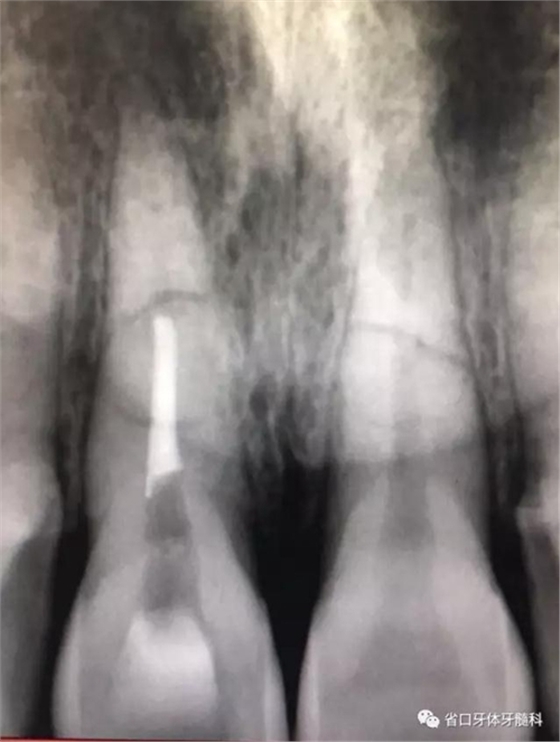

CBCT:11、21頸部以下均見一完全性折裂線,兩牙折裂線均位于頜骨內(nèi)且斷端移位不明顯,相應(yīng)唇側(cè)骨板亦見斷裂且輕度移位。

圖3:11術(shù)前CT

圖4:21術(shù)前